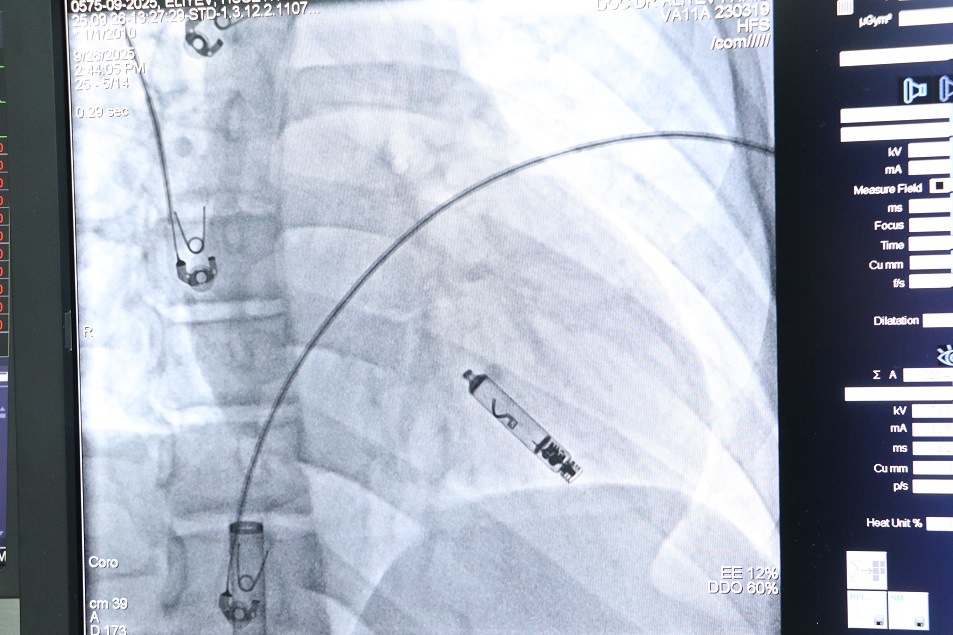

Bakı Sağlamlıq Mərkəzində pasiyentin ürəyinə elektrodsuz kardiostimulyator uğurla implantasiya edilib.

Modern.az xəbər verir ki, Mərkəzin ürək-damar cərrahiyyəsi və kardiologiya məsələləri üzrə koordinatoru, kardioloq-aritmoloq, tibb üzrə fəlsəfə doktoru Dr. Fərid Əliyevin rəhbərliyi ilə aparılan prosedur uğurla başa çatıb.

Qeyd olunur ki, bu əməliyyat artıq bir ilə yaxındır ki, mərkəzdə icra edilir. Lakin bu dəfə pasiyentin xəstəliyinin xüsusiyyətləri nəzərə alınaraq yeni nəsil, aktiv tipli elektrodsuz kardiostimulyator implantasiya olunub.

Həmçinin, bu gün yerləşdirilən sistem təkcə Azərbaycanda deyil, ümumilikdə Qafqaz regionunda ilk dəfə implantasiya edilən cihazdır. Bu uğurlu prosedur, ölkəmizin tibb sahəsində müasir texnologiyaların tətbiqi baxımından atdığı önəmli addımlardan biridir.